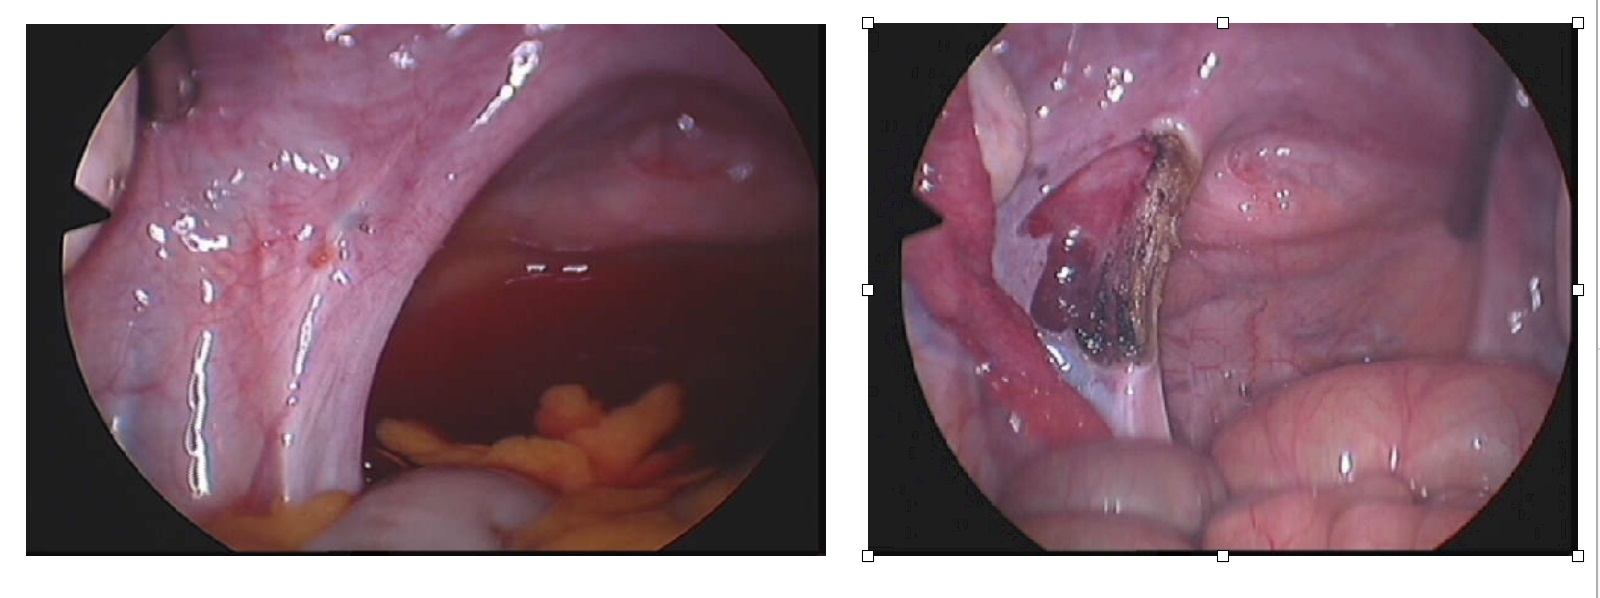

Bladder & Prolapse